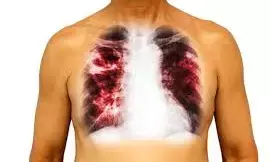

The Institute of Human Virology Nigeria (IHVN) has urged the Federal Government to prioritise early detection, treatment completion, and increased domestic funding to curb the rise of multidrug-resistant tuberculosis (MDR-TB) in Nigeria.

Supreme news reports that MDR-TB is largely caused by incomplete or improper treatment of TB, including skipped doses, wrong drug combinations, poor-quality medicines, or interruptions in drug supply.

It can also occur when individuals are directly infected with already-resistant strains, particularly in areas with weak health systems and delayed diagnosis.